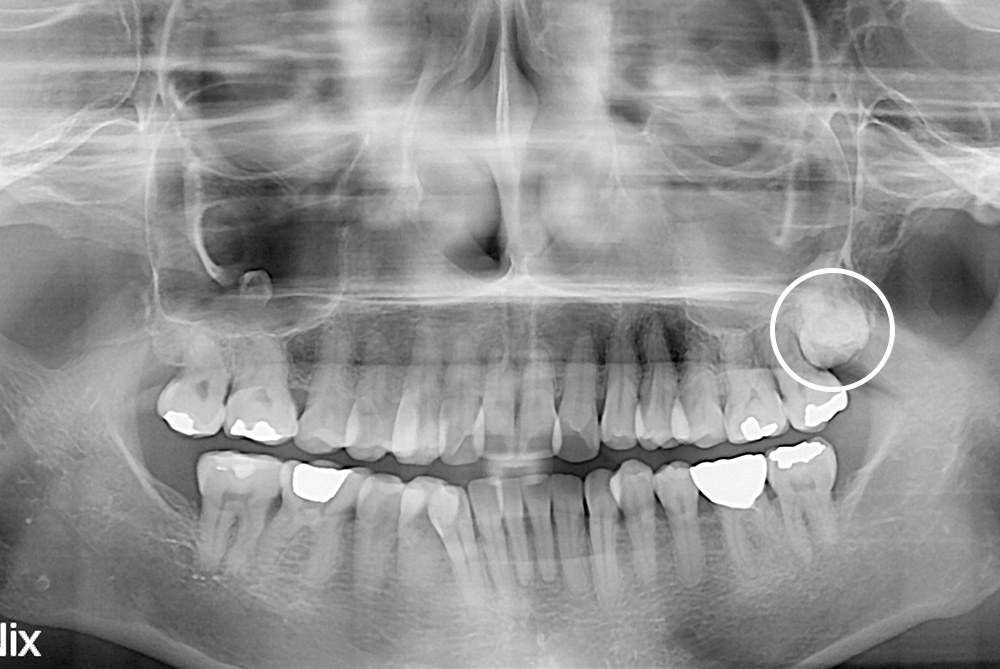

[사랑니] 매복 사랑니 발치

치료전 : 2019-01-10